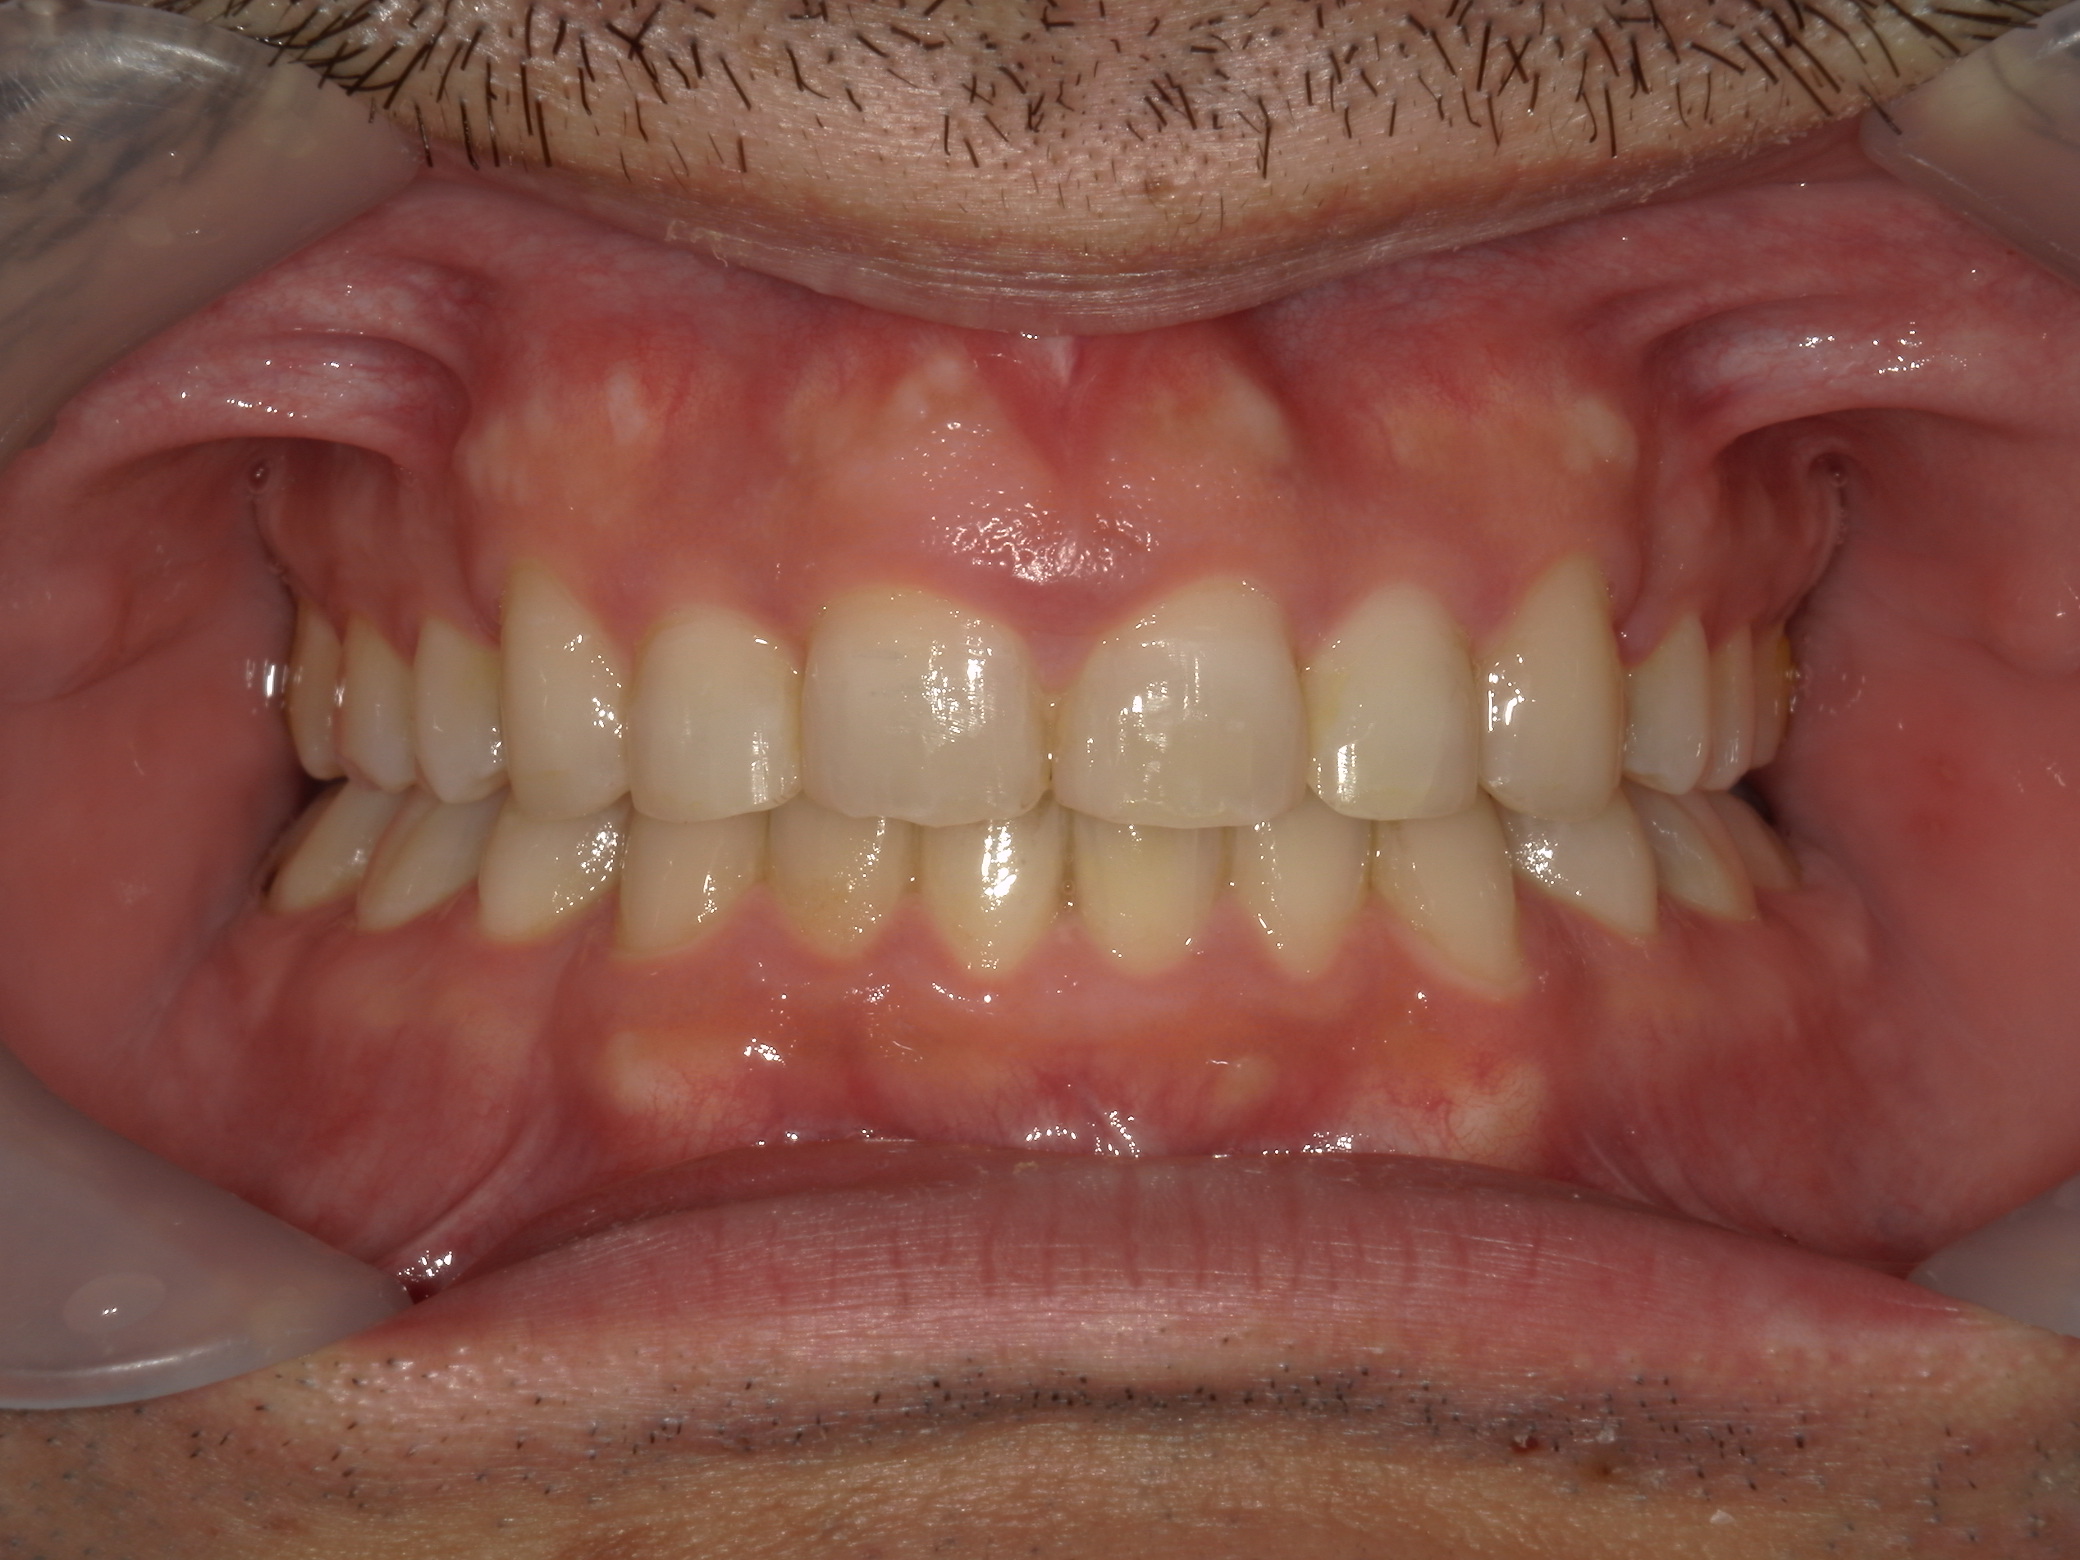

全顎ワイヤー矯正 症例(79)

主訴: 前歯が噛み合わない。歯並びが気になる。

上下左右 第一小臼歯(4本)、上下右 親不知(2本)抜歯。

カテゴリー : ガタガタ(叢生) , 噛み合わせが深い(過蓋咬合)